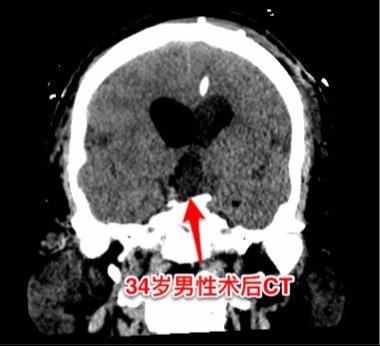

乳头型和造釉型颅咽管瘤的混合型存在吗?34岁男性,广东省惠州市人。一年前因视力下降发现颅咽管瘤,在广东省某医院行开颅手术切除一部分肿瘤。肿瘤复发了来三博脑科医院找我治疗。 第一次手术后病理报告考虑是乳头型颅咽管瘤和造釉型颅咽管瘤的混合型(太罕见了)。手术中还留置了一个动脉瘤夹子、一个Ommaya囊。 昨日作了开颅手术,术中看见肿瘤血供十分丰富,和第三脑室壁及大脑后动脉粘连。手术经历9.5个小时,肿瘤得到完全切除。术后病人的精神状态及四肢活动均很好。希望以后肿瘤不复发。等待病理